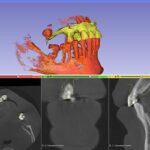

Surgical simulation in 3D Slicer feels a bit like playing a game — just with real anatomy. I tried planning a mock orthognathic case and was honestly impressed by the detail.

You load the CT, segment bones, and define cuts with the Scissors tool. Then you can simulate movements using Transforms.